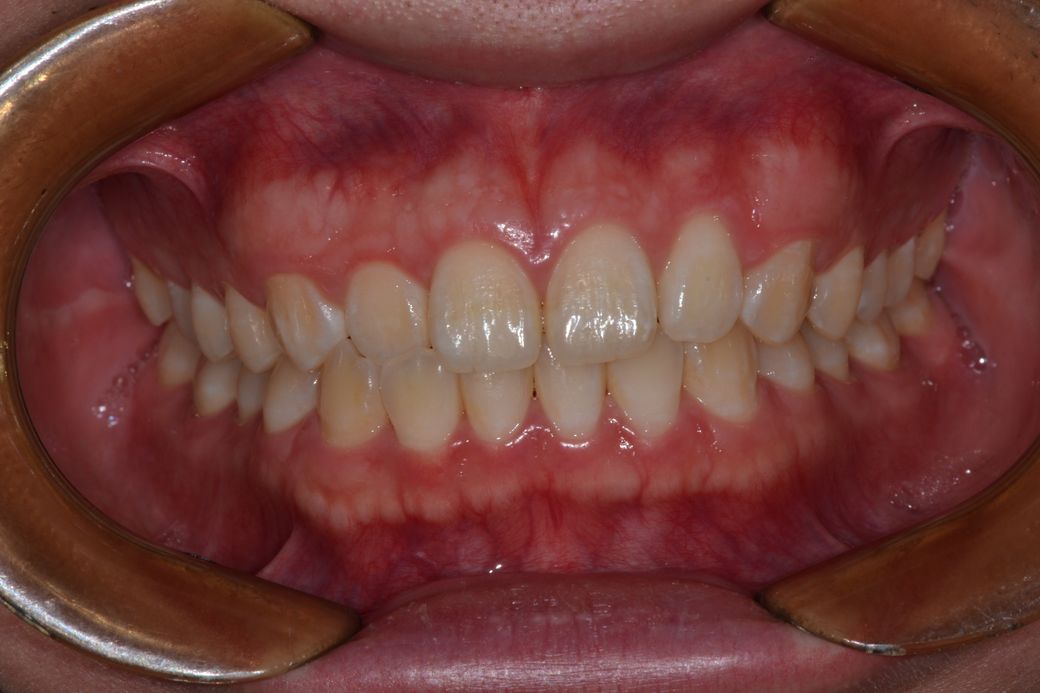

치아 앞니쪽에 반대교합이 있어서 분분교정할 생각인데 부분교정으로 치료가능해 보일까요?

앞니빼고 나머지는 괜찮아 보일까요?

윗니가 아랫니를 덮는 양또는 윗니가 앞으로 나온양이조금 적다고는 하는데 골격적 문제라 어쩔 수 없다는데 맞나요?

부분 교정으로도 어려워 보이며 전체 교정도 현재 증상을 개선하기가 쉽지 않아 보입니다. 워낙 다른 부위에 치열 상태는 나쁘지 않기 때문에 교정을 하더라도 현재 증상에 대한 개선이 어려울 수도 있어 보입니다. 또한 치열 배열 뿐만 아니라 골격적 문제가 동반되고 있어 골격적인 부분은 교정으로 수정할 수가 없습니다.

지금 정도의 골격적 부조화는 일반인들은 알아차리지 못하며 양악 등을 수술을 권하는 정도도 아닙니다.

사진상으로 보면 크게 문제가 있어보이지는 않습니다. 하지만, 기능상으로 문제가 있다면 교정을 하시거나 심미적개선을 원하신다면 교정을 하시면될것같아요.